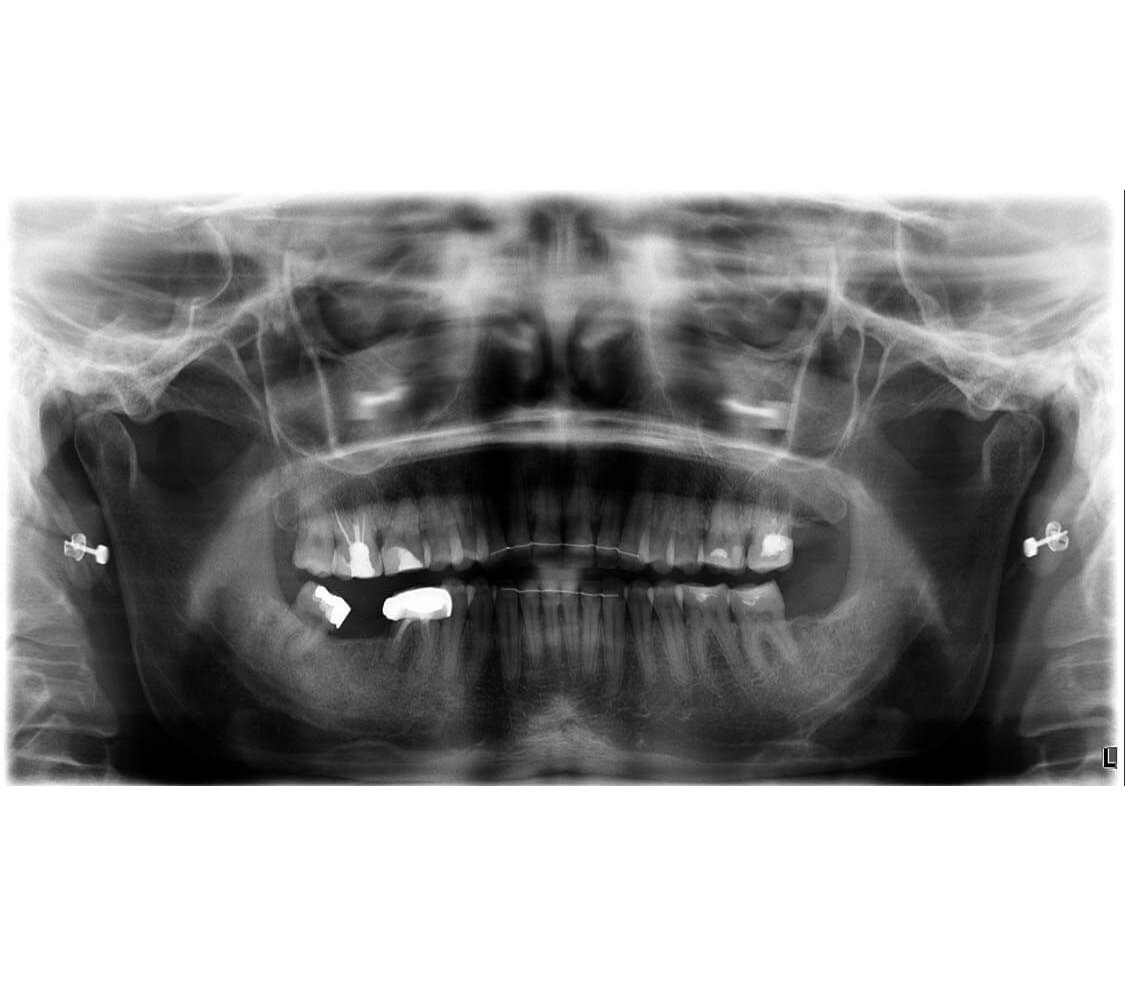

И аз идвам с въпрос. Преди 2,5 месеца ми се наложи да си извадя горен ляв мъдрец. На панорамната снимка се видя гранулом на 6-ти долен ляв зъб. Тази вечер бях при зъболекаря, да видим какво ще го правим. Първо не беше сигурен дали да го отваря, по-спешен му се струвал 7-мия. Но аз от около месец имам леки постоянни болки нощем и реших, че не трябва да отлагам. След като го отвори видя, че зъбчето е болно,но не можа да стигне до края на канала. Продължаваме следващата седмица. Сега се чудя, какво толкова спешно видя на 7-мия зъб. Ако някой разбира - да удари едно рамо: